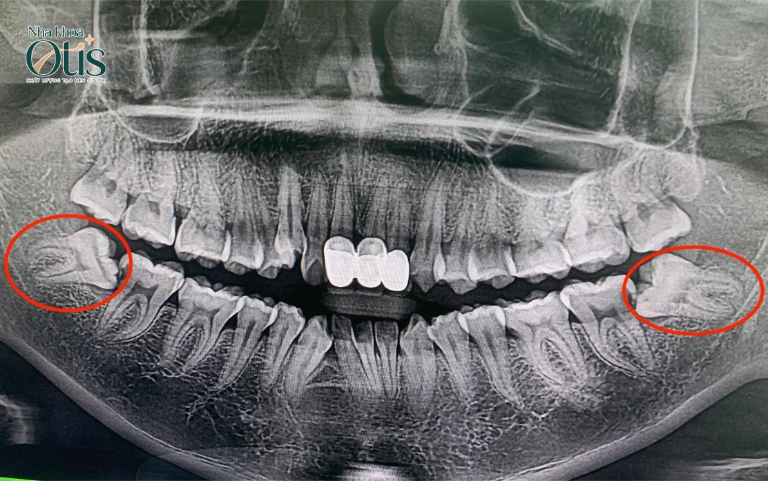

Khác với răng khôn hàm trên, răng khôn hàm dưới nằm sâu trong xương hàm và gần dây thần kinh hàm dưới, dây này chịu trách nhiệm cảm giác cho môi, cằm và lưỡi. Vì vậy, trong một số trường hợp, chân răng mọc lệch hoặc đâm sát dây thần kinh, việc nhổ không đúng kỹ thuật có thể gây tê môi hoặc đau nhức kéo dài.

Bên cạnh đó, răng khôn hàm dưới thường có hình dạng chân răng cong, phân nhánh hoặc nằm ngang, khiến việc tiếp cận và lấy răng khó khăn hơn. Nếu không có thiết bị hỗ trợ hiện đại như chụp CT 3D ConeBeam, bác sĩ sẽ khó xác định chính xác vị trí răng và dây thần kinh, dẫn đến nguy cơ tổn thương mô xung quanh.

Thông thường, bác sĩ nha khoa luôn khuyến khích nhổ răng khôn trong độ tuổi răng khôn mọc từ 18-30 hoặc khi có các dấu hiệu răng khôn đau nhức. Cần thăm khám và nhổ răng khôn ngay trong các trường hợp răng khôn mọc lệch, mọc ngầm hoặc chen chúc tránh các biến chứng khác như viêm tấy, sưng nề kéo dài.

- Răng khôn mọc lệch, mọc ngầm